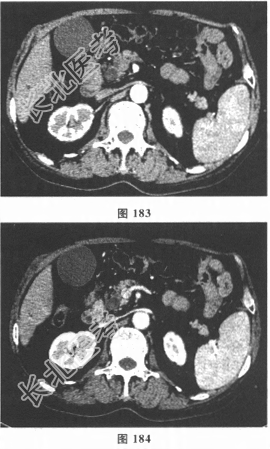

- 多项选择题2.该患者入院后查肝功能生化及肿瘤标志物:ALT143.3U/L, AST174.8U/L,Alb33.7g/L, TB81.1μmol/L,DB65.1μmol/L, ALP393.2U/L,GGT482.5U/L; CA19-9215U/ml;CEA0.6U/ml; AFP3.1ng/ml;CA125 12.3U/ml; 乙肝、丙肝、HIV、梅毒检查均阴性;影像学结果见图183~图186。该患者的临床诊断应考虑( )

A、胰头癌

F、胆管下段癌

G、壶腹周围癌